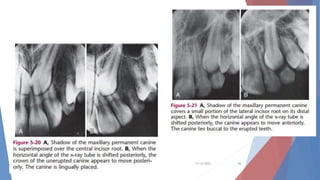

Localization Techniques

Tube-Shift Localization (Clark)

SLOB Rule

Same Lingual Opposite Buccal

One method of localizing embedded or unerupted teeth uses the

buccal object rule, which states that the image of any buccally

oriented object appears to move in the opposite direction from a

moving x-ray source. On the other hand, the image of any

lingually oriented object appears to move in the same direction

as a moving x-ray source .